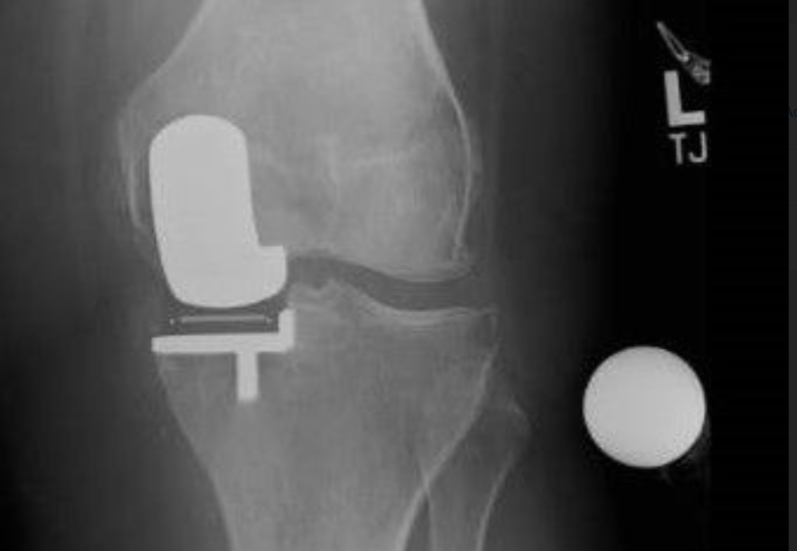

Partial Knee Replacement

Selective replacement of the affected knee compartment with maintenance of normal areas and knee ligaments